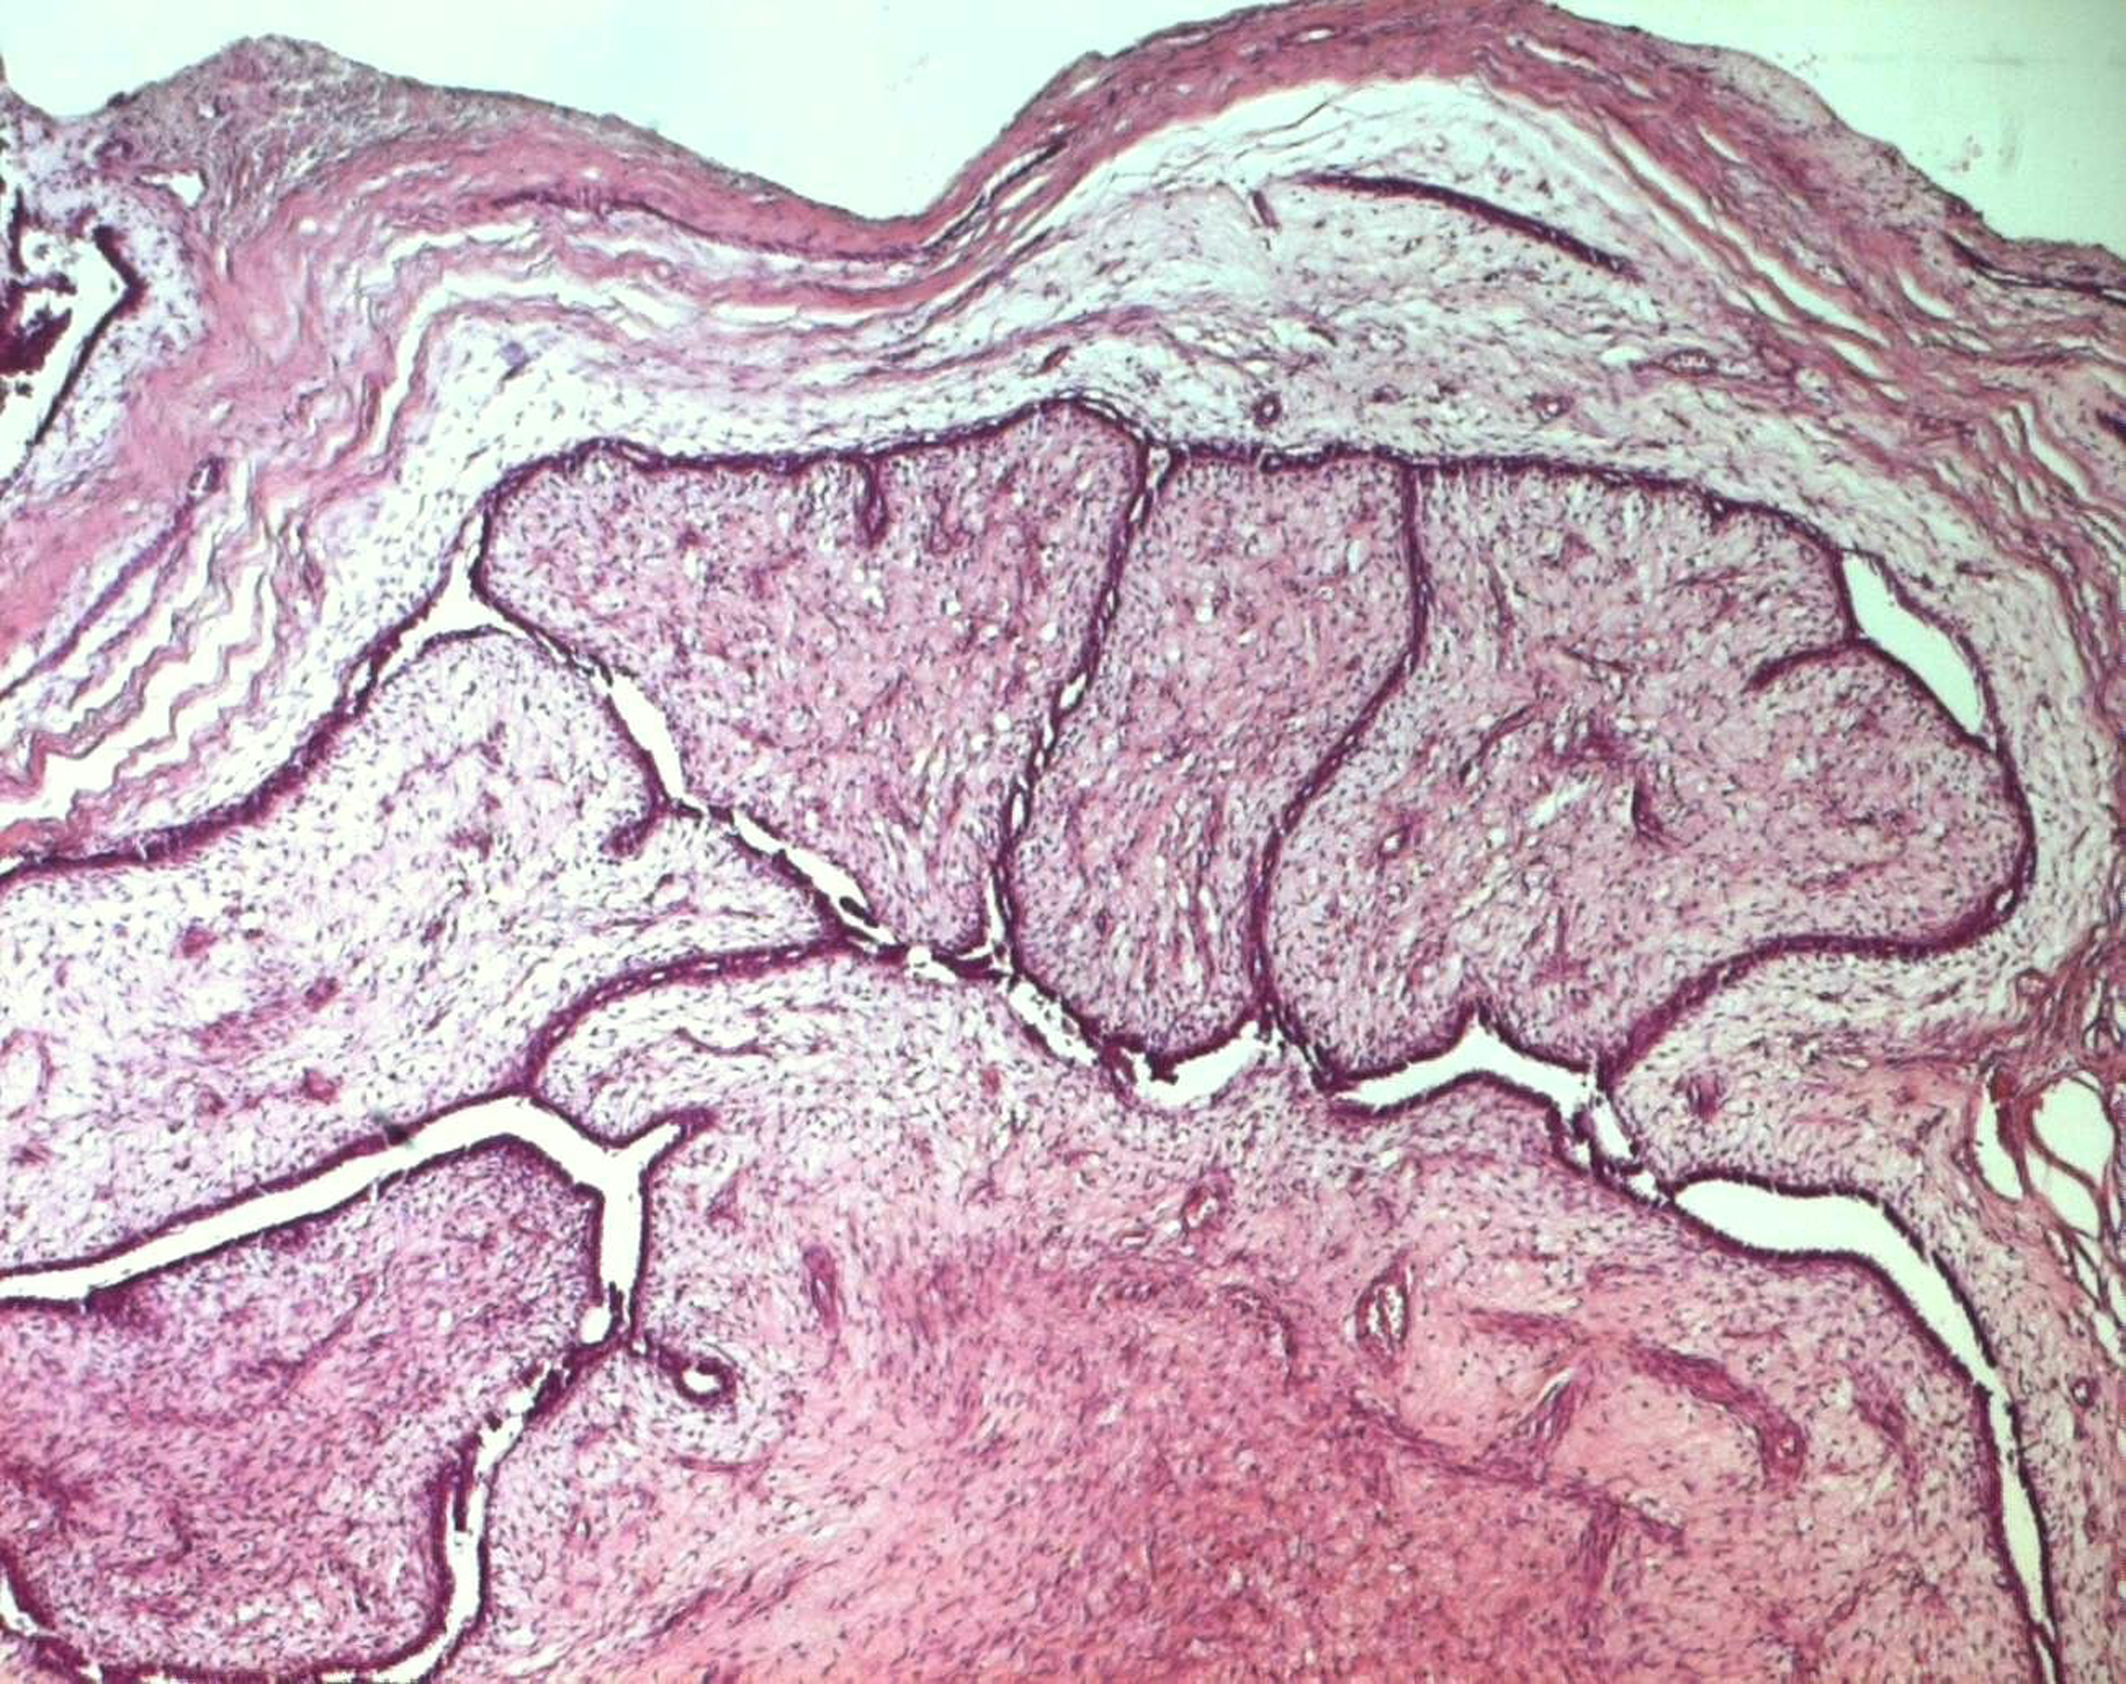

Surgical treatment was primarily applied in all cases, consisting in lumpectomy in 21 cases and total mastectomy in 5 cases (4 malignant PTs and 1 borderline PT). Frozen-section analysis was undertaken in 19 cases. It was concordant with final histology in 14 cases. Three out of the 5 remaining cases were benign PTs at the final histology and assessed as fibroadenomas in frozen-section analysis. One borderline PT at the final histology was assessed as malignant PT at frozen-section analysis and one borderline PT was incorrectly assessed as benign at frozen-section analysis. On gross appearance, tumors ranged in size from 1.5 to 40 cm (mean 7.8 cm), 14 tumors were larger than 5 cm. The size range for benign, borderline, and malignant tumors was 1.5 to 40 cm (mean: 7.4 cm), 1.7 to 15 cm (mean: 7.5 cm), and 3.6 to 23.4 cm (mean: 9 cm), respectively. On histological examination, 13 tumors were graded as benign (Fig. 3), 7 tumors as borderline (Fig. 4) and 6 tumors as malignant (Fig. 5).

![]() Click for large image | Figure 3. Benign phyllodes tumor: a well-circumscribed biphasic neoplasm containing leaf-like, epithelial-lined papillary projections penetrating into cystic spaces (HE x 40). |